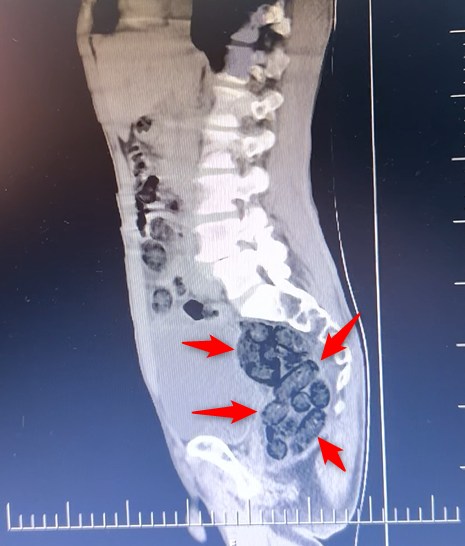

Otobüste yolcu olarak bulunan yabancı uyruklu bir şahsın midesinde yapılan kontrollerde, 64 parça halinde toplam 472 gram metamfetamin maddesi ele geçirildi.